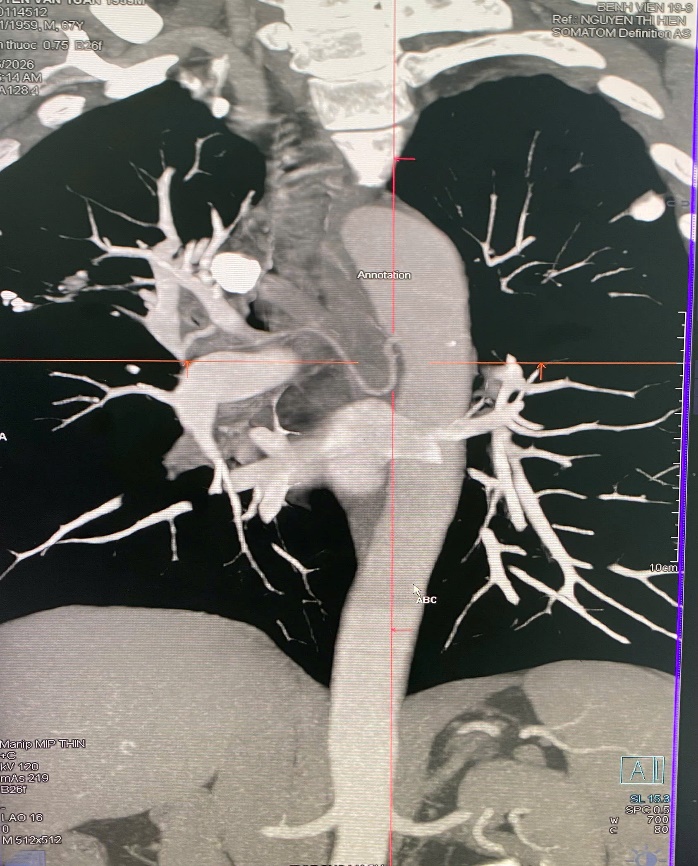

Ngày 25/02, bệnh nhân nhập viện tại Bệnh viện 19-8 để thăm khám và điều trị. Qua thăm khám lâm sàng, kết hợp các phương tiện chẩn đoán hình ảnh hiện đại, các bác sĩ phát hiện bệnh nhân bị giãn động mạch phế quản bên phải – nguyên nhân trực tiếp gây tình trạng ho máu kéo dài.

Hình ảnh giãn động mạch phế quản phải.